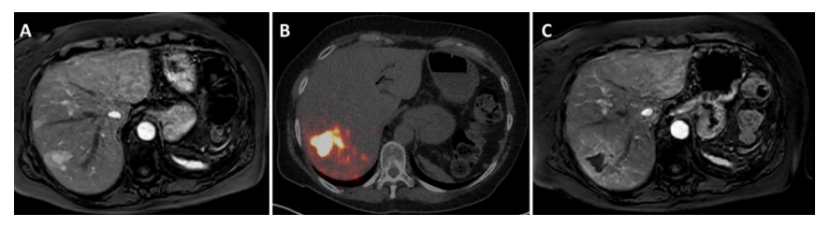

SIRT作為胰腺NELM二線療法 A:Whipple切除術后接受4周期PRRT治療,第7肝段有較大病灶,附近有多個衛星病灶,不適合手術切除/消融;B:SIRT后,第7肝段靶病灶吸收劑量為300Gy;C:SIRT后3個月顯示腫瘤完全壞死,輻射引起周圍健康肝組織一定程度的改變